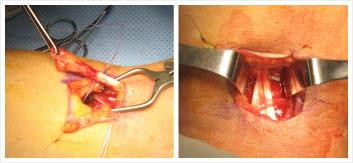

Examples: X-ray of broken humerus

Repair of torn biceps tendon